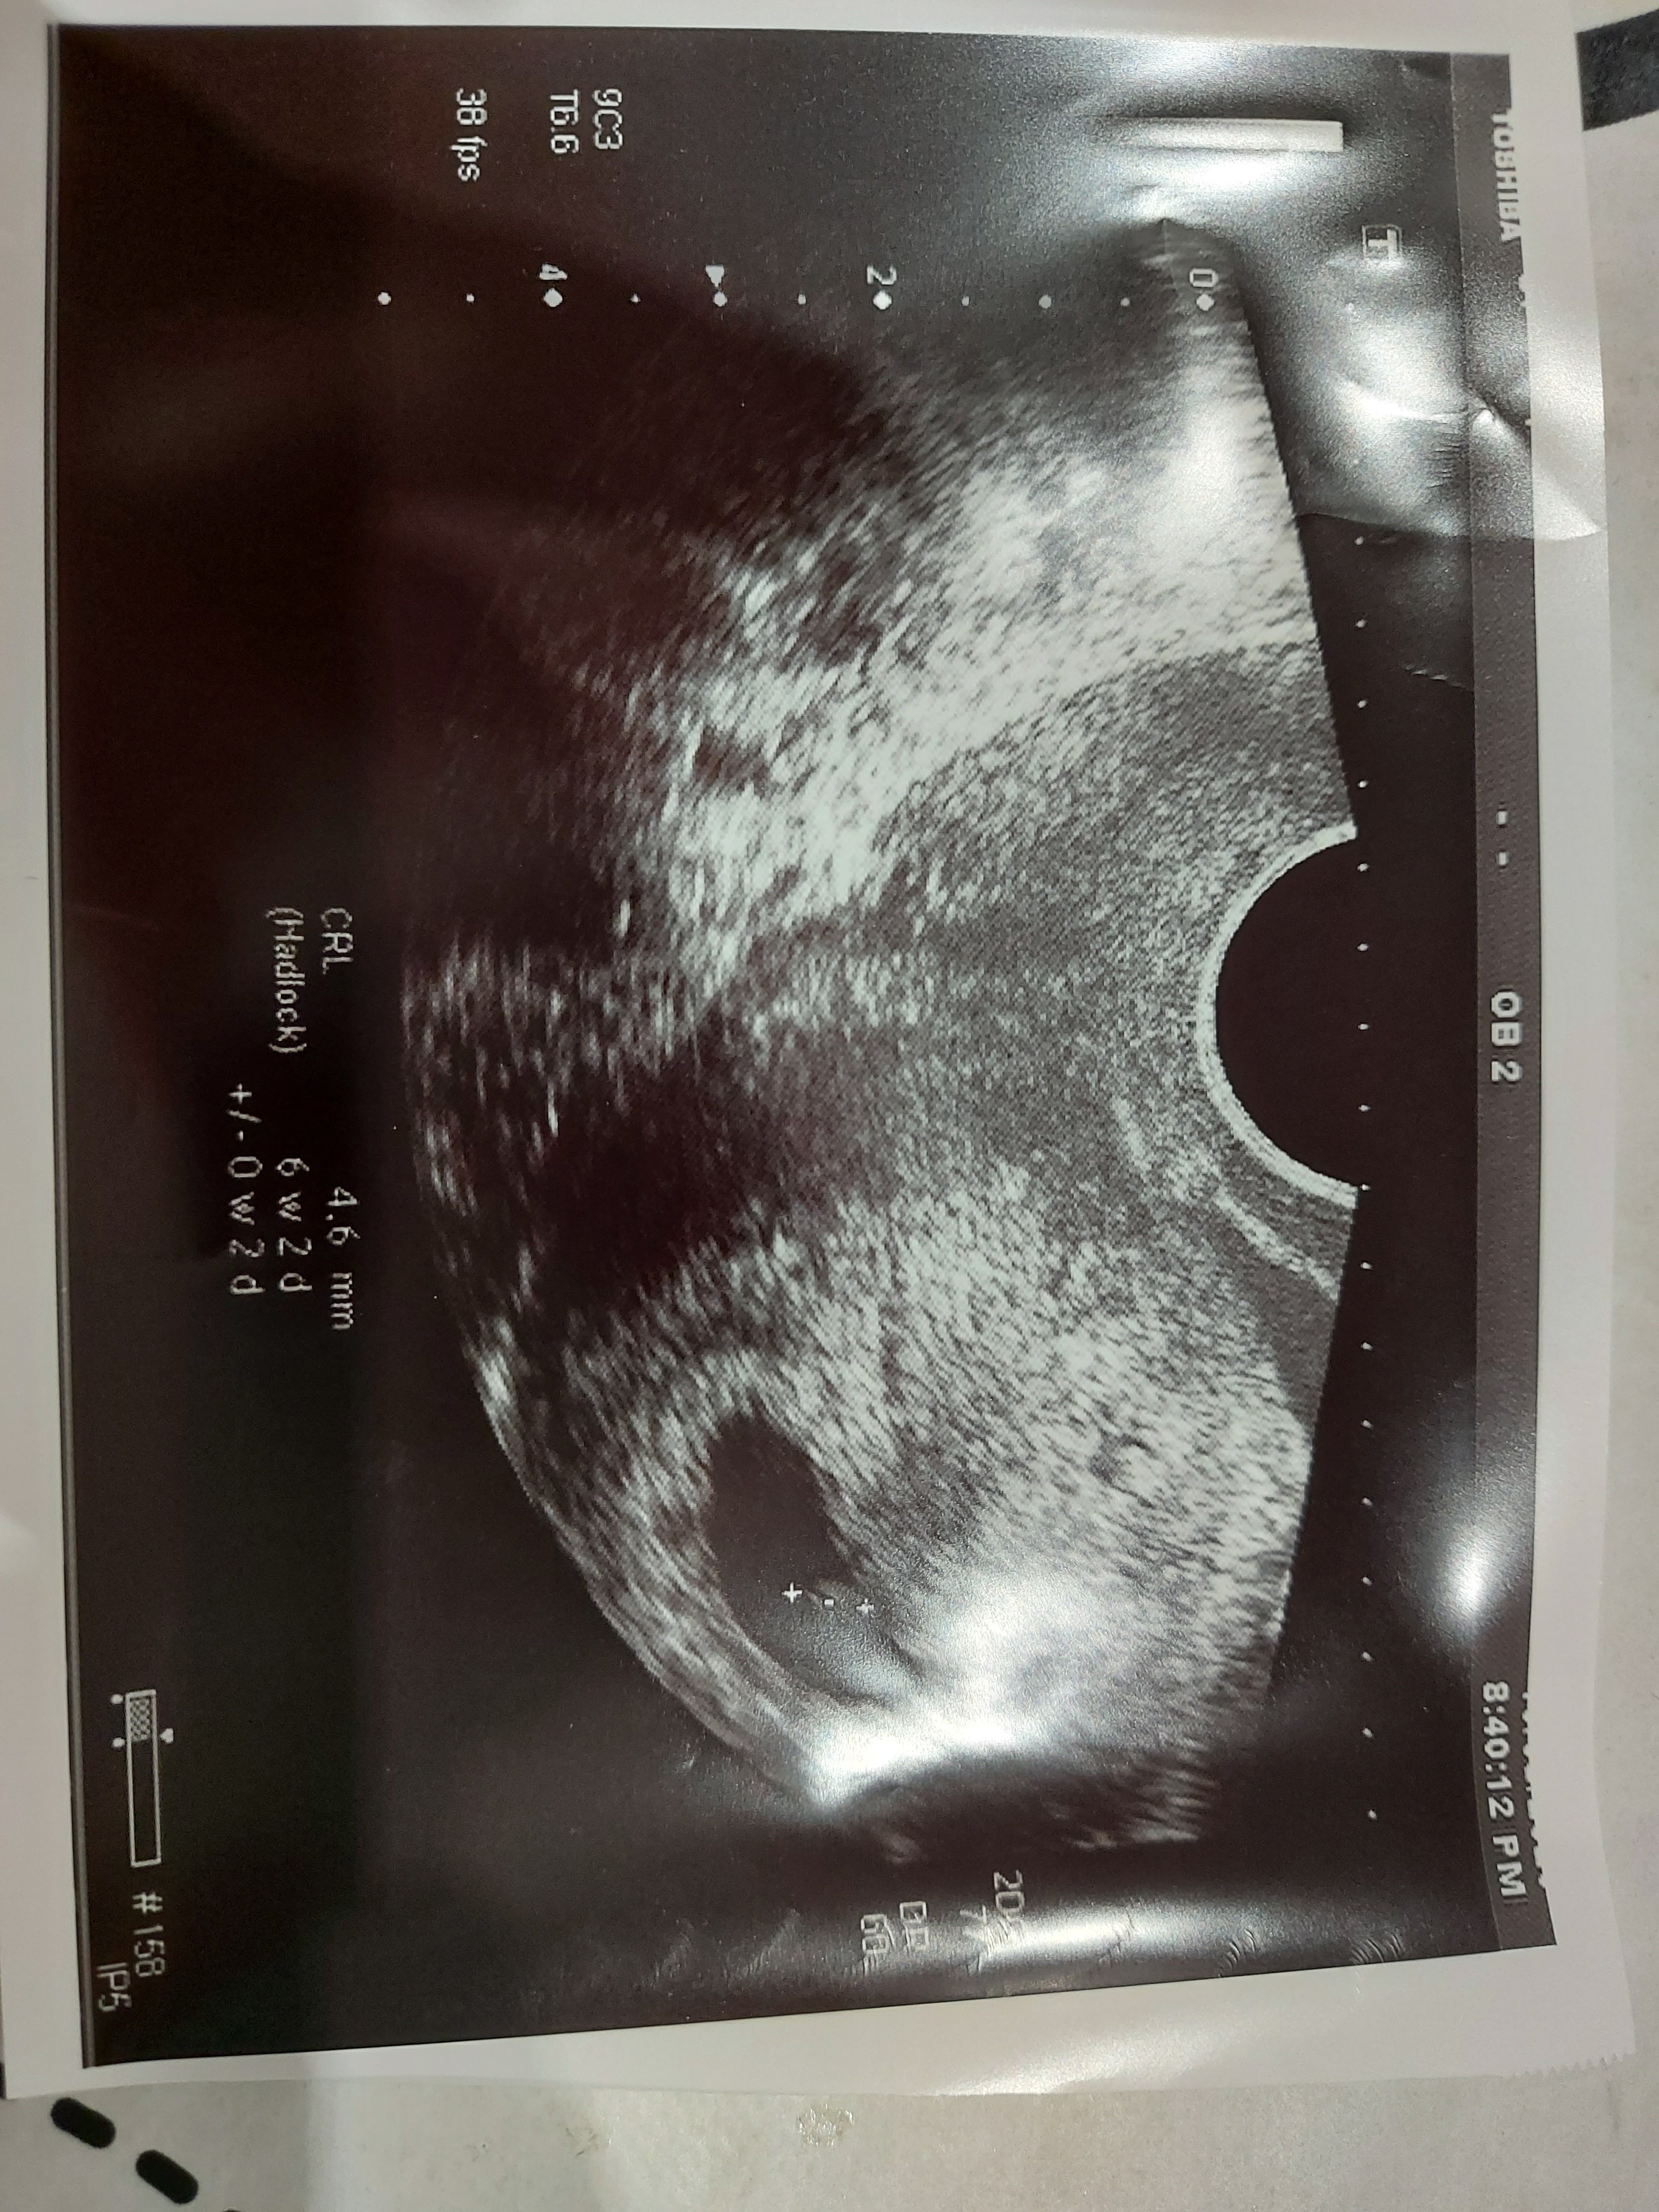

Dziewczyny ktore maja zdjecia z bardzo wczesnej ciazy zerknijcieZobacz załącznik 1163133

Hej, ja mam zdjęcie prawie identyczne jak Ty, a mi jednak lekarz tak długo szukał serduszka, aż znalazłZwariuje do wizyty we wtorek, moja polozna mi napisala ze jakosc usg fatalna i moze cos jest z boku pecherzyka z lewej strony, a nie pusty, ale za slaby sprzet zeby to oceniac...